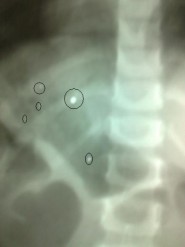

– وصل مستشفى عفيف 8 حالات أحدهما لإمرأه وحالتها خطيره وأربع نساء حالتهن متوسطة ورجلين حالتهما متوسطة أحدهمافلسطيني الجنسية وطفلة حالتها مستقره .

– دخول المرأة التي حالتها خطيره الى قسم العناية المركزة إثر نزيف بالرأس .